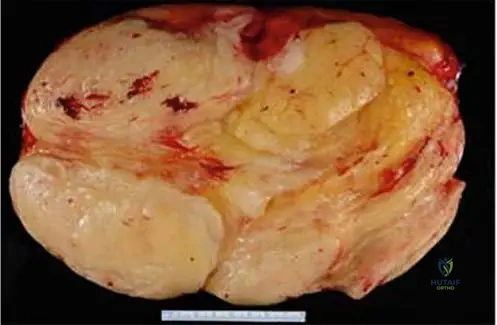

Enlarged clinical image